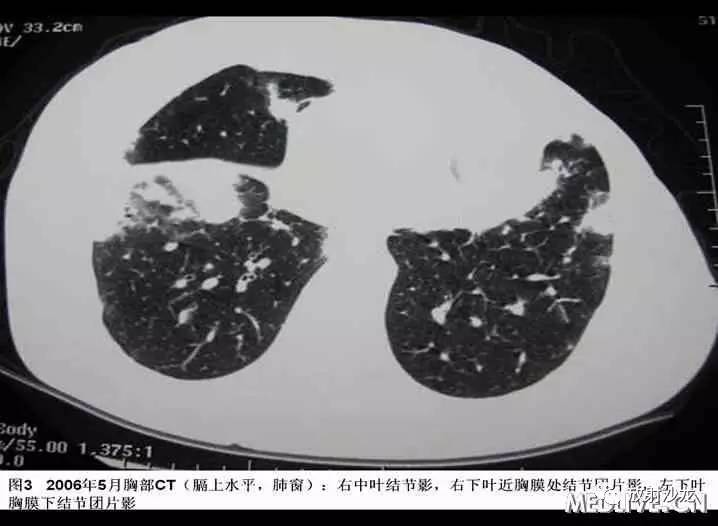

患者于2006年4月初无诱因出现间断咳嗽,少量黄痰,无咯血、胸闷、胸痛。2006年4月中下旬出现发热,最高体温38℃,当地血常规:WBC:6.7G/L,GR:78%,胸片示“右下肺纹理增粗,局部可见斑片索条影,右侧肋膈角钝”;考虑“肺部感染”,予拜复乐(莫西沙星)、罗氏芬(头孢曲松)治疗3天后体温降至正常,但仍有间断咳嗽、咯痰,遂于2006年5月中旬就诊某一上级医院,胸部CT“右下肺及胸膜下可见多发结节、斑片影,局部可见支气管扩张”(见图1-4),行胸腔镜肺活检,病理经多家医院综合会诊后考虑“淋巴组织增生性病变,但是诊断淋巴瘤证据不足”,未予特殊治疗。